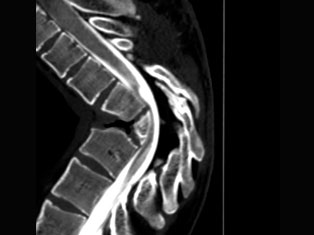

Spinal Tumors

A spinal tumor is a growth that develops within your spinal canal or within the bones of your spine. A spinal cord tumor, also called an intradural tumor, is a spinal tumor that that begins within the spinal cord or the covering.